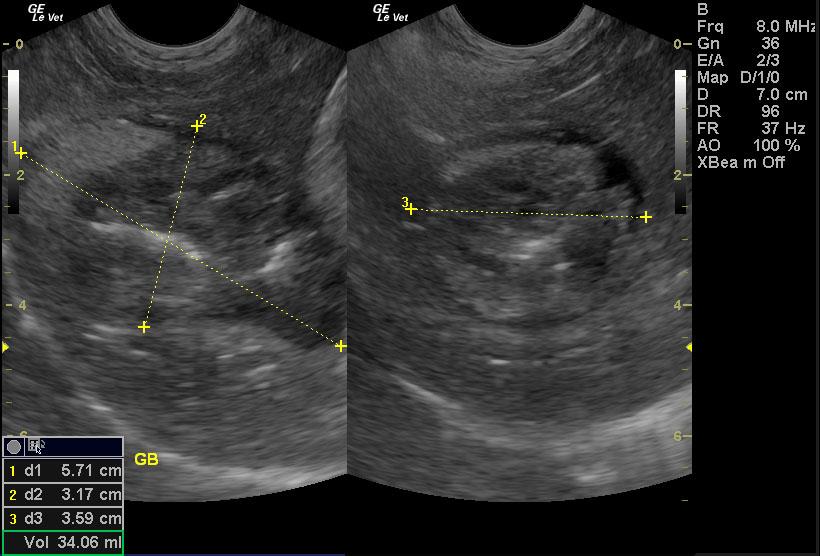

A 15 year old female spayed mixed canine with a history of decreased appetite, diarrhea, and ataxia was presented for evaluation of being unable to walk, weak and lethargic, anorexic, and possible seizures. Abnormalities on serum biochemistry were severely elevated liver enzyme activity, bilirubinemia, hypokalemia, and elevated pre-prandial bile acids. Systolic blood pressure was normal.